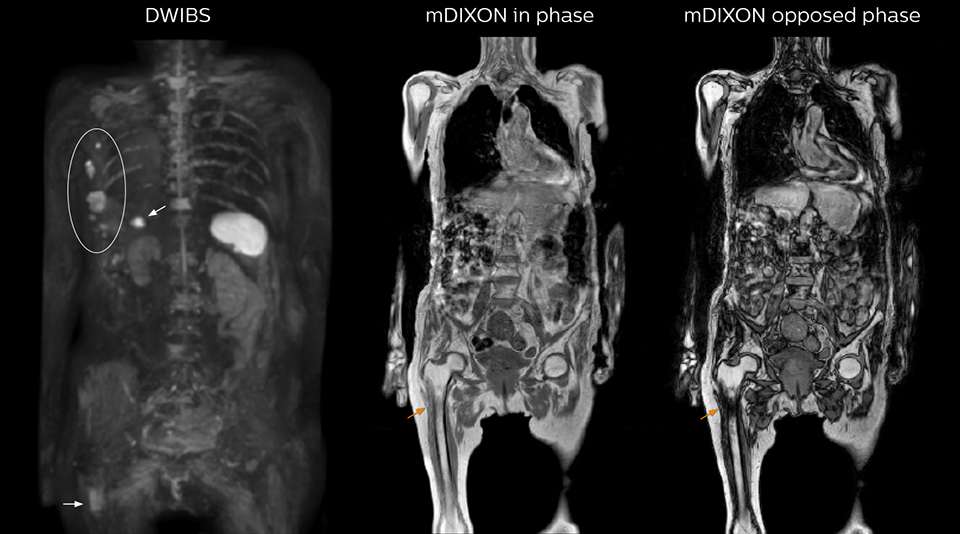

“mDIXON FFE allows us to quickly get information we need to assess the presence of fat. That gives us more information when we need to diagnose bone lesions, and when we are asked to judge fat-containing lesions such as hepatocellular or renal carcinoma,” Dr. Nobusawa says. “The mDIXON fat images can help us to differentiate fatty bone marrow from bone lesions. This is especially useful in elderly people, who tend to have fattier bone marrow. The water images provide a high signal-to-noise ratio in the intestinal canal, which is valuable for visualizing lesions in the colon,” he says.

Kawasaki Sawai Hospital’s whole body protocol also includes an mDIXON FFE sequence. Because mDIXON provides images for four contrast types – water only, fat only, in-phase and out-of-phase – from a single acquisition, it is useful in many ways.

“In-phase and out-phase sagittal T1-weighted FFE images help us to visualize and further characterize bone lesions such as metastasis and bone-marrow hyperplasia that have high signal on DWI. These images are also used throughout radiotherapy, to monitor changes in the fatty bone marrow.”